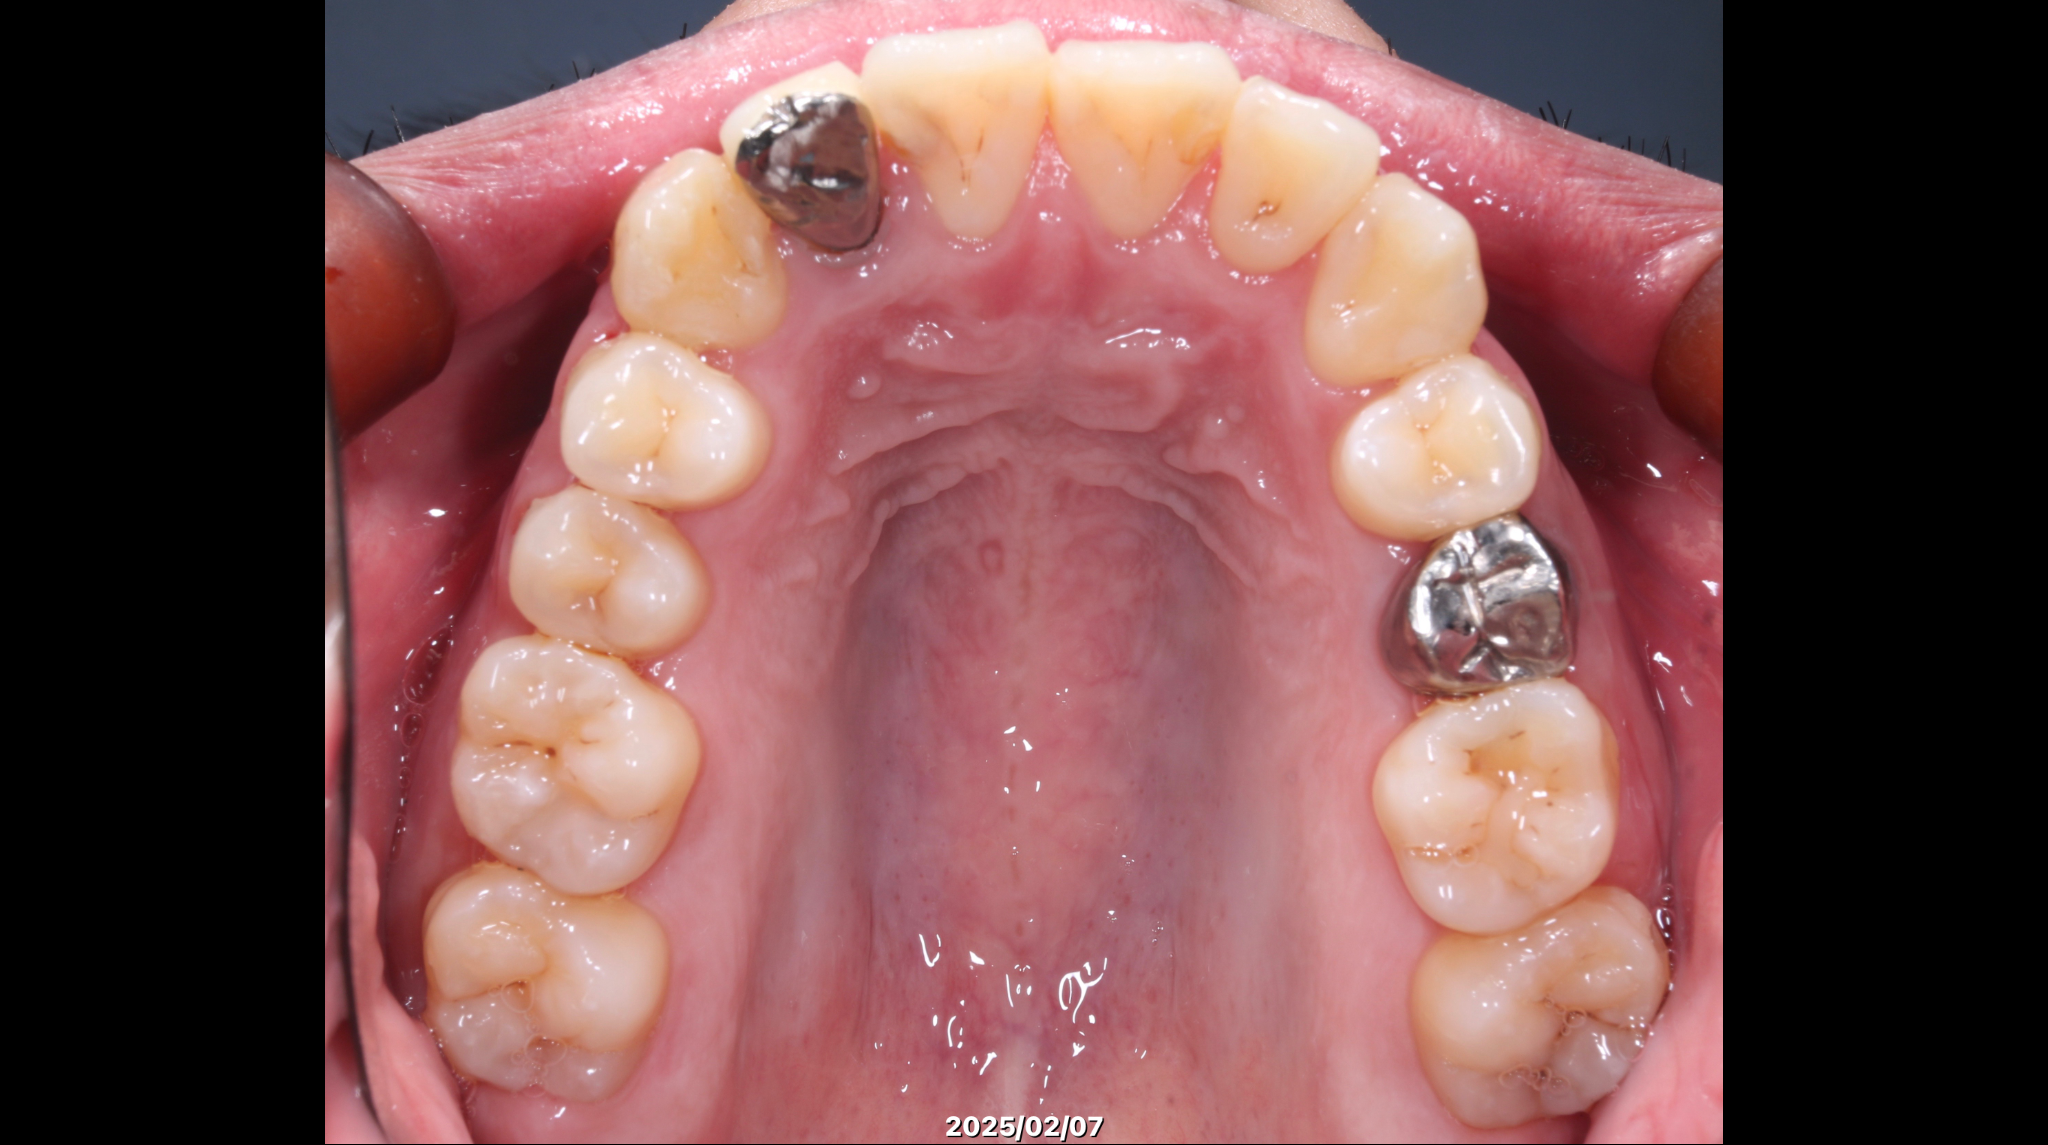

症例2:叢生を矯正治療で改善した症例

術前の状態

治療概要

| 患者さんの状態 | 叢生 |

|---|---|

| 治療内容 | MEAWを用いた矯正治療(非抜歯) |

| 治療期間 | 約2年 |

| 治療費用 | 1,320,000円(税込) ※矯正治療費のみです。 |

| 治療のリスク | 歯肉退縮、自由診療、後戻り、口腔内清掃が難しい |